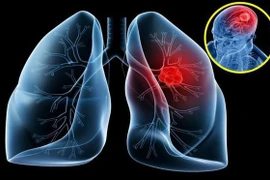

Chỉ khoảng 19% bệnh nhân ung thư phổi nói chung có thời gian sống thêm ≥ 5 năm ở tất cả các giai đoạn được chẩn đoán. Đối với giai đoạn IV, thời gian sống thêm 5 năm rất thấp, chỉ khoảng 2%. Cần biết dự phòng, phát hiện sớm.

56% bệnh nhân ung thư phổi trên thế giới được chẩn đoán ở giai đoạn IV. Tỷ lệ sống còn 5 năm ước tính sau chẩn đoán ung thư phổi giai đoạn cuối chỉ 6.3%. Vì vậy, cần nhận biết để phát hiện sớm.